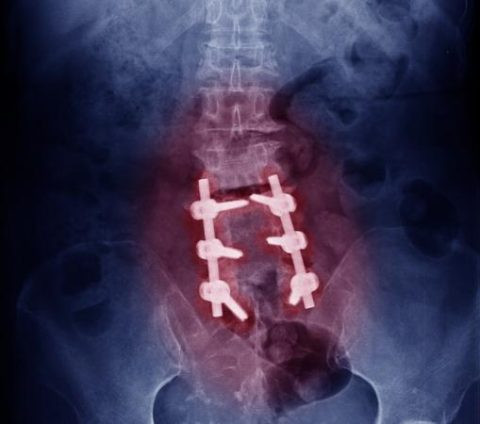

The surgeon places a bone graft between the affected vertebrae.

Metal plates, rods, or screws may be used to secure the spine.

Over time, the bones fuse to create a solid structure.